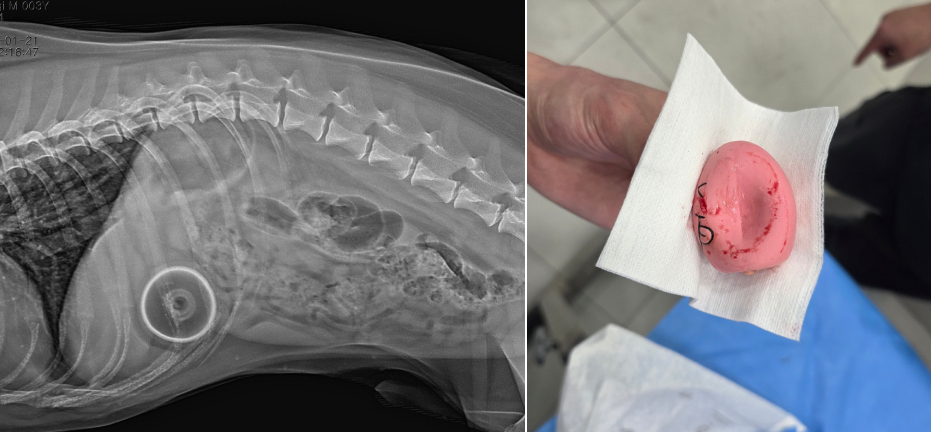

종양 제거 수술

종양의 크기와 위치, 전이 가능성을 고려해 수술 범위를 결정합니다. 정확한 진단과 함께 삶의 질을 고려한 치료 계획을 수립합니다.